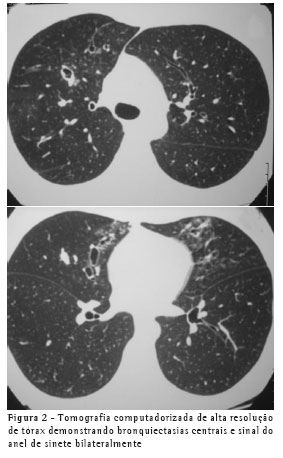

A avaliação clínica revelou roncos e sibilos difusos bilaterais. Os exames subsidiários mostraram: espirometria normal, teste alérgico cutâneo imediato (Prick teste) positivo para A. fumigatus, hemograma com eosinofilia (13%), IgE sérica total maior que 1.000 ng/ml, teste sérico para determinação de IgE específica (RAST) para A. fumigatus classe 3. Na radiografia simples de tórax observaram-se imagens de opacidade em "dedo de luva" no terço superior direito (Figura 1) e na tomografia computadorizada de alta resolução, bronquiectasias centrais (Figura 2).

De acordo com os achados de inúmeros trabalhos, as alterações observadas na radiografia de tórax de pacientes com ABPA têm sido descritas como imagens de consolidações extensas e de infiltrado alveolar, que ocorrem predominantemente nos lobos superiores, e imagens que espelham impactação mucóide num brônquio central. A imagem em "dedo de luva" e a imagem em "pasta de dente" são imagens transitórias de impactação de muco que podem desaparecer com a tosse ou com o uso de corticóide.(7-9) A paciente apresentou, na radiografia simples de tórax, sinais de opacidade em "dedo de luva" no terço superior do hemitórax direito (Figura 1) e, na tomografia computadorizada de alta resolução, sinais de bronquiectasias centrais (Figura 2). Segundo a literatura, sinais de opacidade em "dedo de luva" são sugestivos de ABPA,(10) refletindo a inflamação, espessamento e dilatação da árvore brônquica, devidos à impactação de muco nas vias aéreas.(11) Para a detecção de bronquiectasias centrais, a tomografia computadorizada de alta resolução é sugerida como o melhor método diagnóstico, tendo em vista que, para essa finalidade, a radiografia de tórax não é sensível e nem específica.(4)